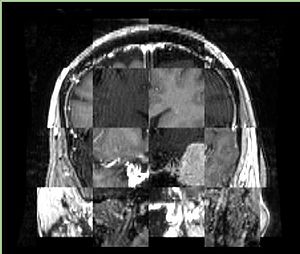

• Checkerboard appearance of unregistered images for the representative data of interest

• Case01